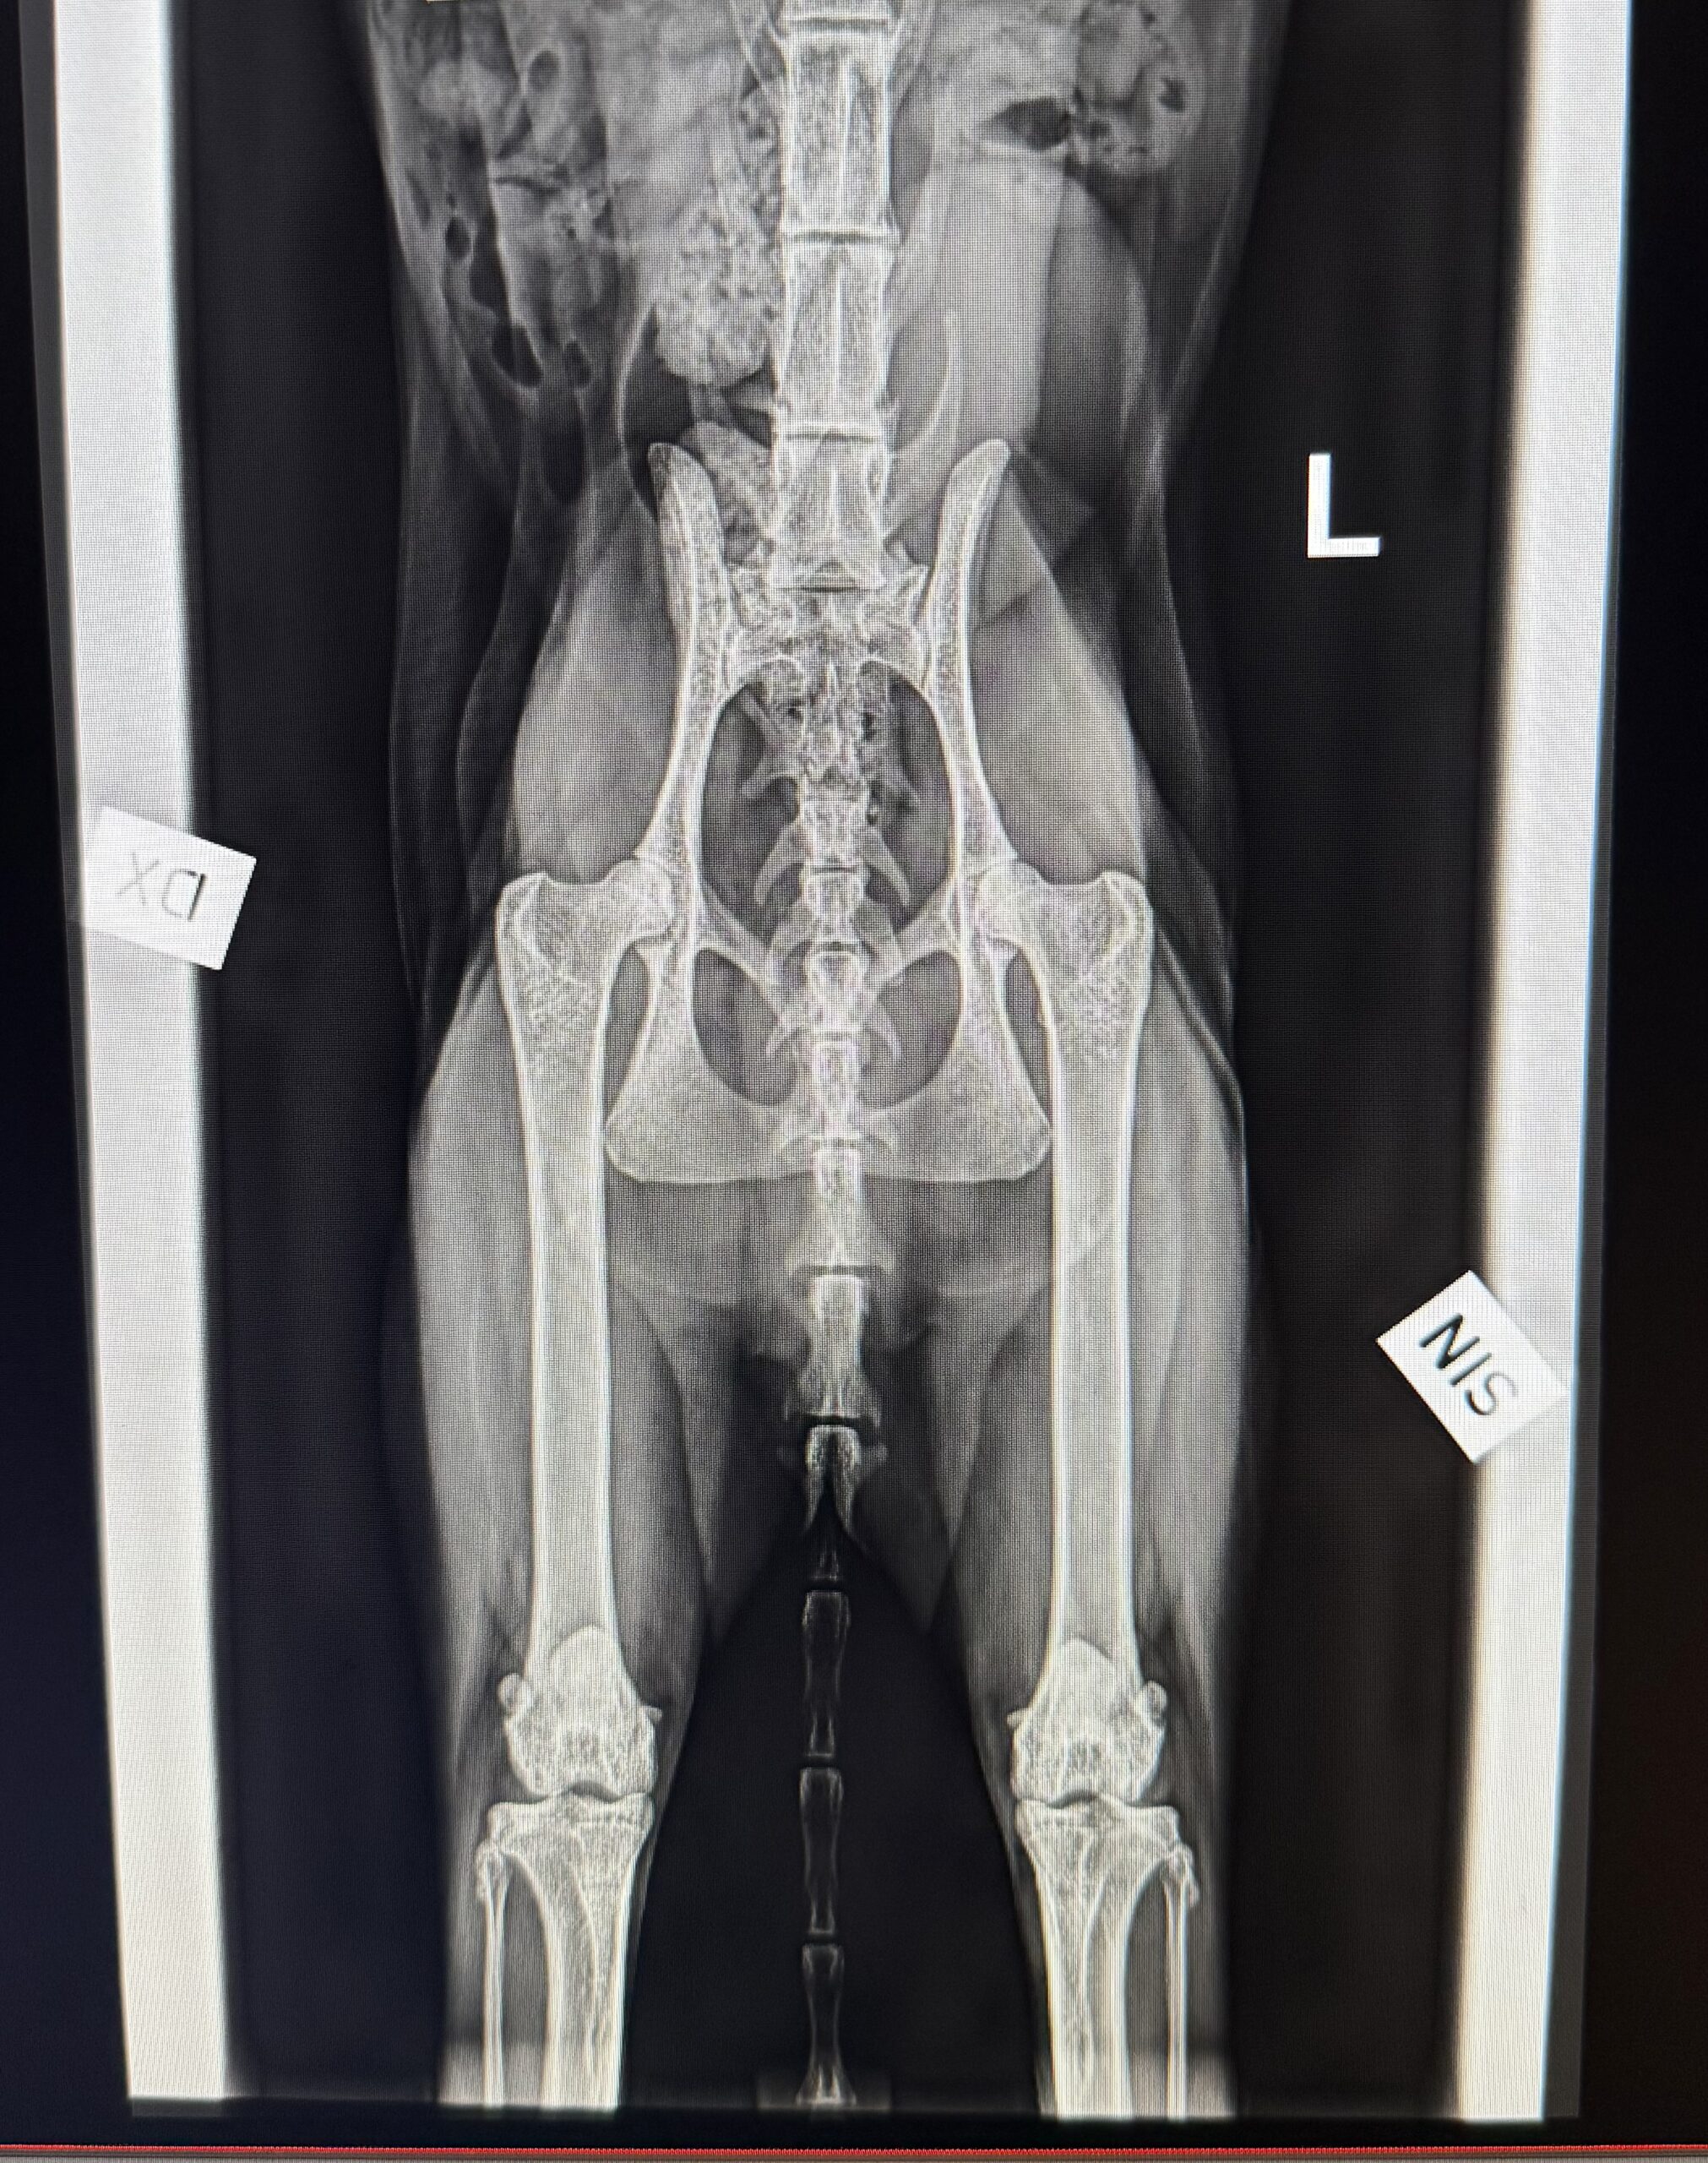

Och ja – vi röntgar även katter! 🐱 På sista bilden ser ni en HD-bild på en Maine Coon.